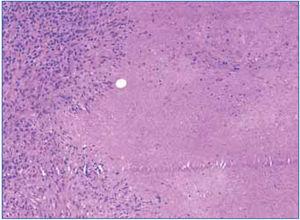

Given the clinical (severe renal failure), radiological (kidneys of normal size and echostructure) and laboratory findings (anaemia, proteinuria and microscopic haematuria), a renal biopsy was performed in which interstitial inflammation at the expense of lymphocytes was detected, accompanied by histiocytes, which formed granulomas at several points (Figure 2 and 3). One of these contained multinucleated Langhans giant cells. Glomeruli were normal. Granular material occupied the tubules and the epithelium was flattened. There were no microorganisms in the PAS or Ziehl-Nielsen stain.

c) Tuberculosis with granulomatous interstitial involvement (our primary hypothesis). Included in the histological data of the biopsy supporting this hypothesis is the presence of Langhans cell granulomas, although caseous necrosis was not observed. The absence of acid-alcohol resistant bacilli in the renal biopsy and the lack of PCR of the sample prevents us from concluding that granulomatous interstitial nephritis due to tuberculosis was the definite diagnosis.2 However, the clinical picture of pulmonary tuberculosis and caseous necrosis in the cervical adenopathy biopsy almost certainly confirm the diagnosis.

Figure 3. Interstitial lymphocytic infiltrate and epithelioid granuloma in the renal biopsy

Figure 4. Detail of the interstitial infiltrate